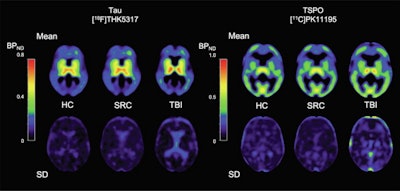

Image shows mean THK5317 and PK11195 nondisplaceable binding potential (BPND) for controls, rSRC and TBI patients, depicting tau and translocator protein (TSPO) expression, as well as corresponding standard deviation images. In symptomatic rSRC athletes, a voxel-wise t-test showed clusters of significantly increased THK5317 binding in the corpus callosum and subcortically including the medial temporal region and PK11195 binding in the medial temporal lobes. In TBI, elevated tau and TSPO binding was observed in the thalamus, temporal lobe white matter and midbrain. Significant group differences in total tau load were found between healthy controls and rSRC in subcortical gray matter (SRC 7.5 ± 0.9, controls 6.7 ± 0.5, p = 0.038), although not between TBI patients and controls. No significant differences in the number of voxels with THK5317 BPND > 0.5 or skewness in BPND distribution were found. Image courtesy of NeuroImage: Clinical.Ultimately, the results showed that PET tracers for tau and neuroinflammation can be used to identify long-term, postinjury increases in tau aggregation and microglial activation in young, symptomatic athletes with a history of three or more concussions, as well as in young adult patients with a single moderate-severe TBI. The data imply persistent pathology at prolonged postinjury time points and are supported by the increased CSF and serum NFL levels, the authors wrote.